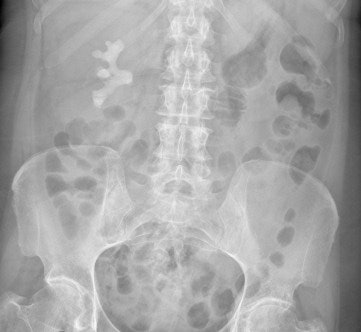

Abdominal radiography (AXR) constitutes an important part of the routine work-up of patients presenting with acute abdominal pain at most emergency departments, but an abnormal abdominal radiograph is notoriously difficult to interpret and a normal abdominal x-ray is misleading because it can miss various conditions. This is causing many hospitals to amend its procedures.

To evaluate the efficacy of AXR in the assessment of acute abdominal pain, and to provide evidence for a change of imaging practice, Yamamoto and colleagues conducted a retrospective analysis of abdominal x-rays performed for acute admissions to the emergency department and any subsequent imaging with CT or ultrasound. They included only patients who complained of abdominal pain, were aged older than 16, and were referred initially for AXR.